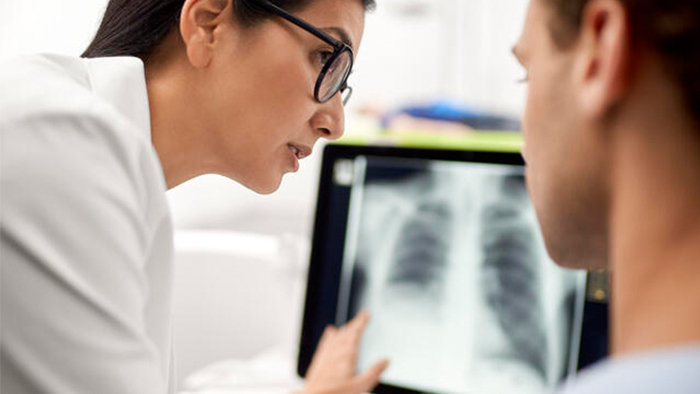

At Philips, our X-ray and Fluoroscopy equipment offer excellent workflow and quality images to drive through-put and confident diagnoses while enabling high staff and patient satisfaction. There’s no limit to what we can do together. Because today health knows no bounds, and neither should healthcare.

Digital Radiography